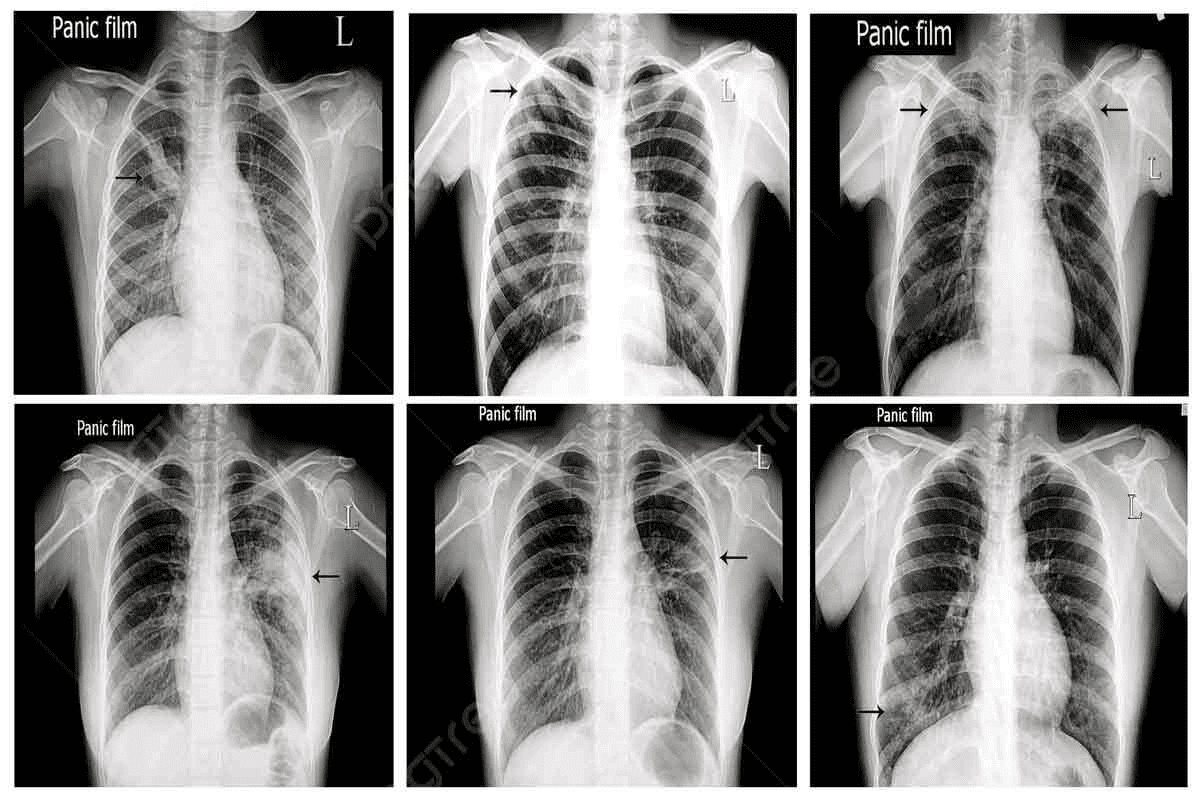

Detecting Bone Metastasis: Diagnostic Methods

Diagnosing bone metastasis requires imaging and lab tests. These methods help find bone metastasis early. This is key for knowing the cancer stage and prognosis.

Bone Scan Metastasis Detection

Bone scans are a common way to find bone metastases. A small amount of radioactive material is injected into the blood. This material goes to active bone areas. A camera then shows these areas on images.

Key benefits of bone scan metastasis detection include:

- High sensitivity for detecting bone metastases

- Ability to image the entire skeleton

- Useful for monitoring response to treatment

CT, MRI, and PET Imaging

Other imaging methods are also important. Computed Tomography (CT) scans give detailed body images. Magnetic Resonance Imaging (MRI) shows soft tissues and bones well. Positron Emission Tomography (PET) scans find cancer areas by showing metabolic activity.